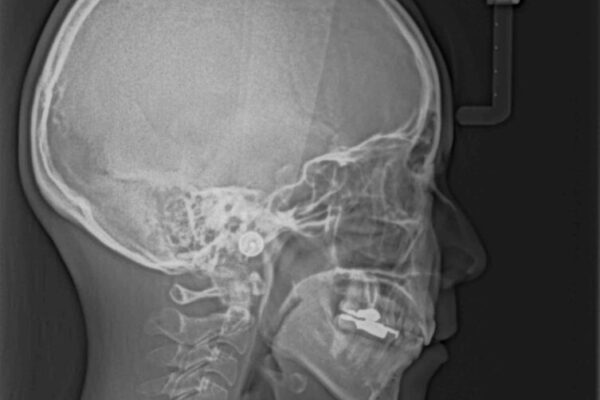

前歯のデコボコと上顎の前突感による口の閉じにくさを気にして来院された患者様です。

治療計画

目立たない装置を希望されたので、上顎が裏側装置のハーフリンガルを選択し、上下左右の小臼歯(計4歯)を抜歯して矯正治療を行うこととしました。

治療前